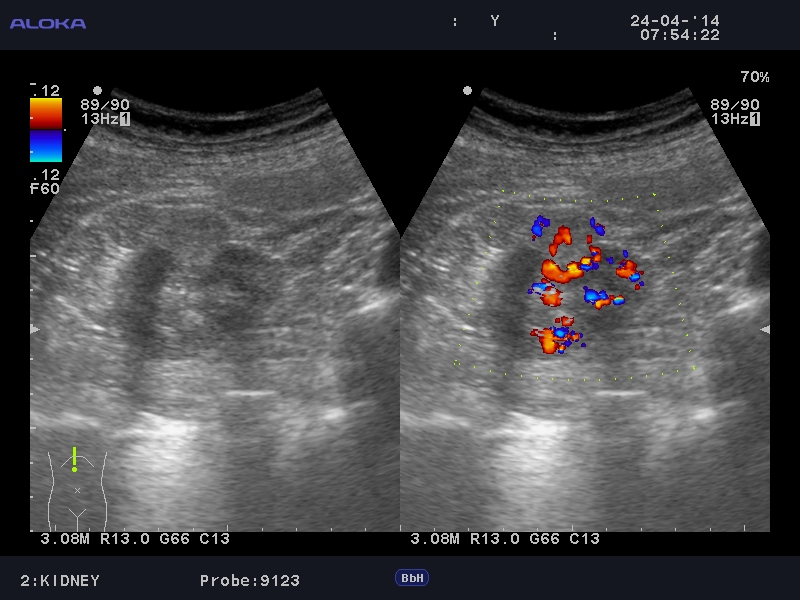

Онкоцитома почки - УЗИ

Женщина 76 лет. Жалоб не предъявляет.

t6_20140424_ABDOMEN_0002.JPG